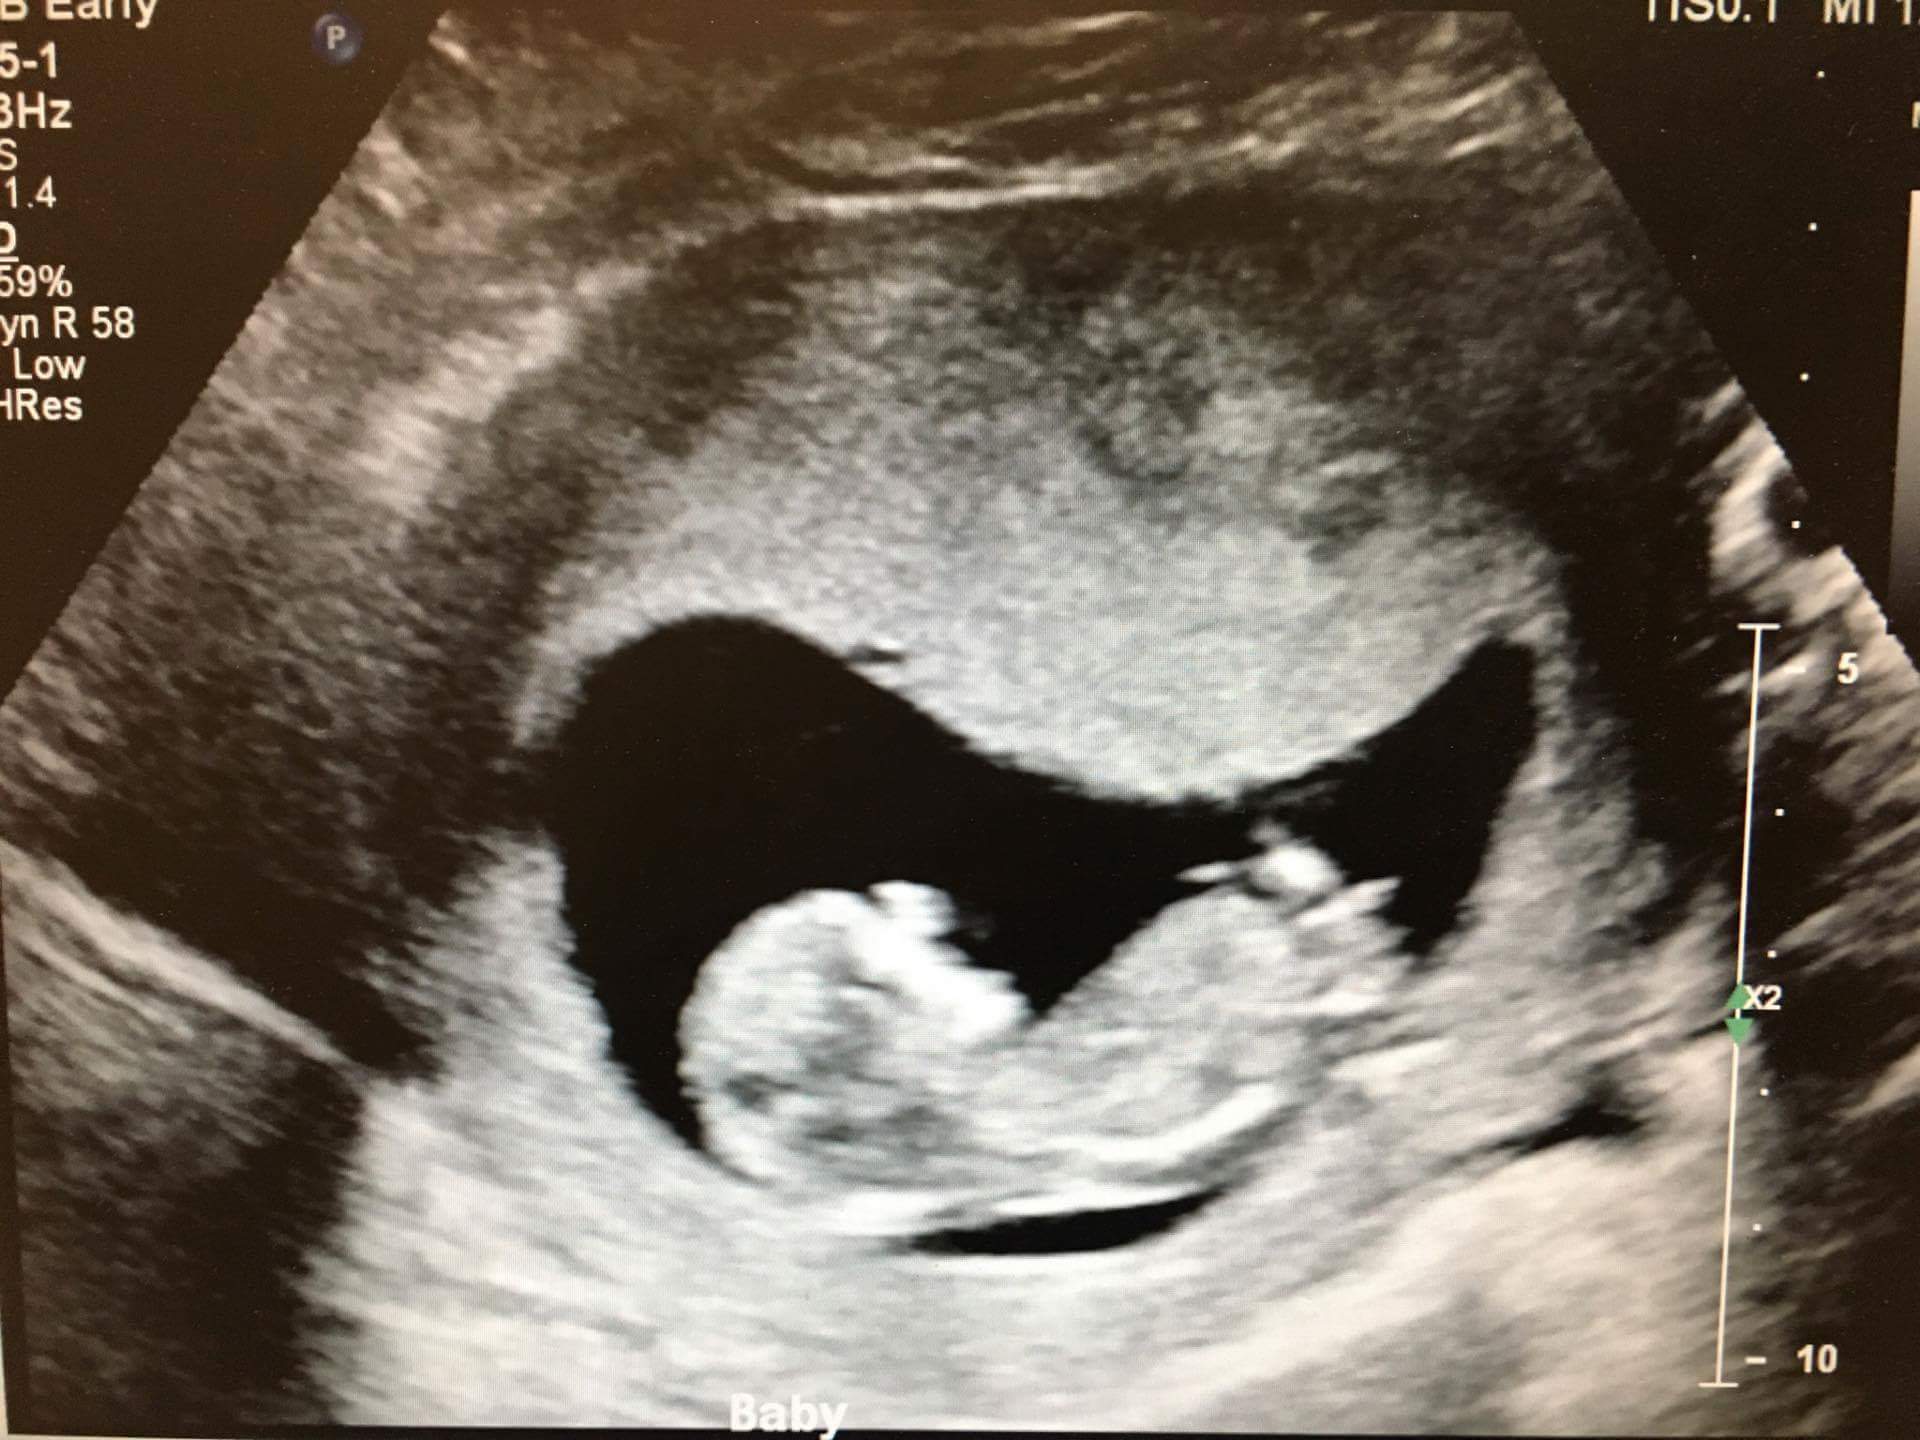

My friend is pregnant with baby number 4. She currently has 3 of the same gender. Wondering if she'll have four of a kind or finally mix things up a bit. =)

The scan is from 12w2d.

A bit earlier than I like to guess, but looking girly so far!

I dont think that nub will rise. This looks girlie to me :) Any chance we can know with a few guesses in now what her other 3 are? would she have all girls or would this be her first :)

Thanks for the guesses. =) She has 3 boys now, so I hope you are all right!